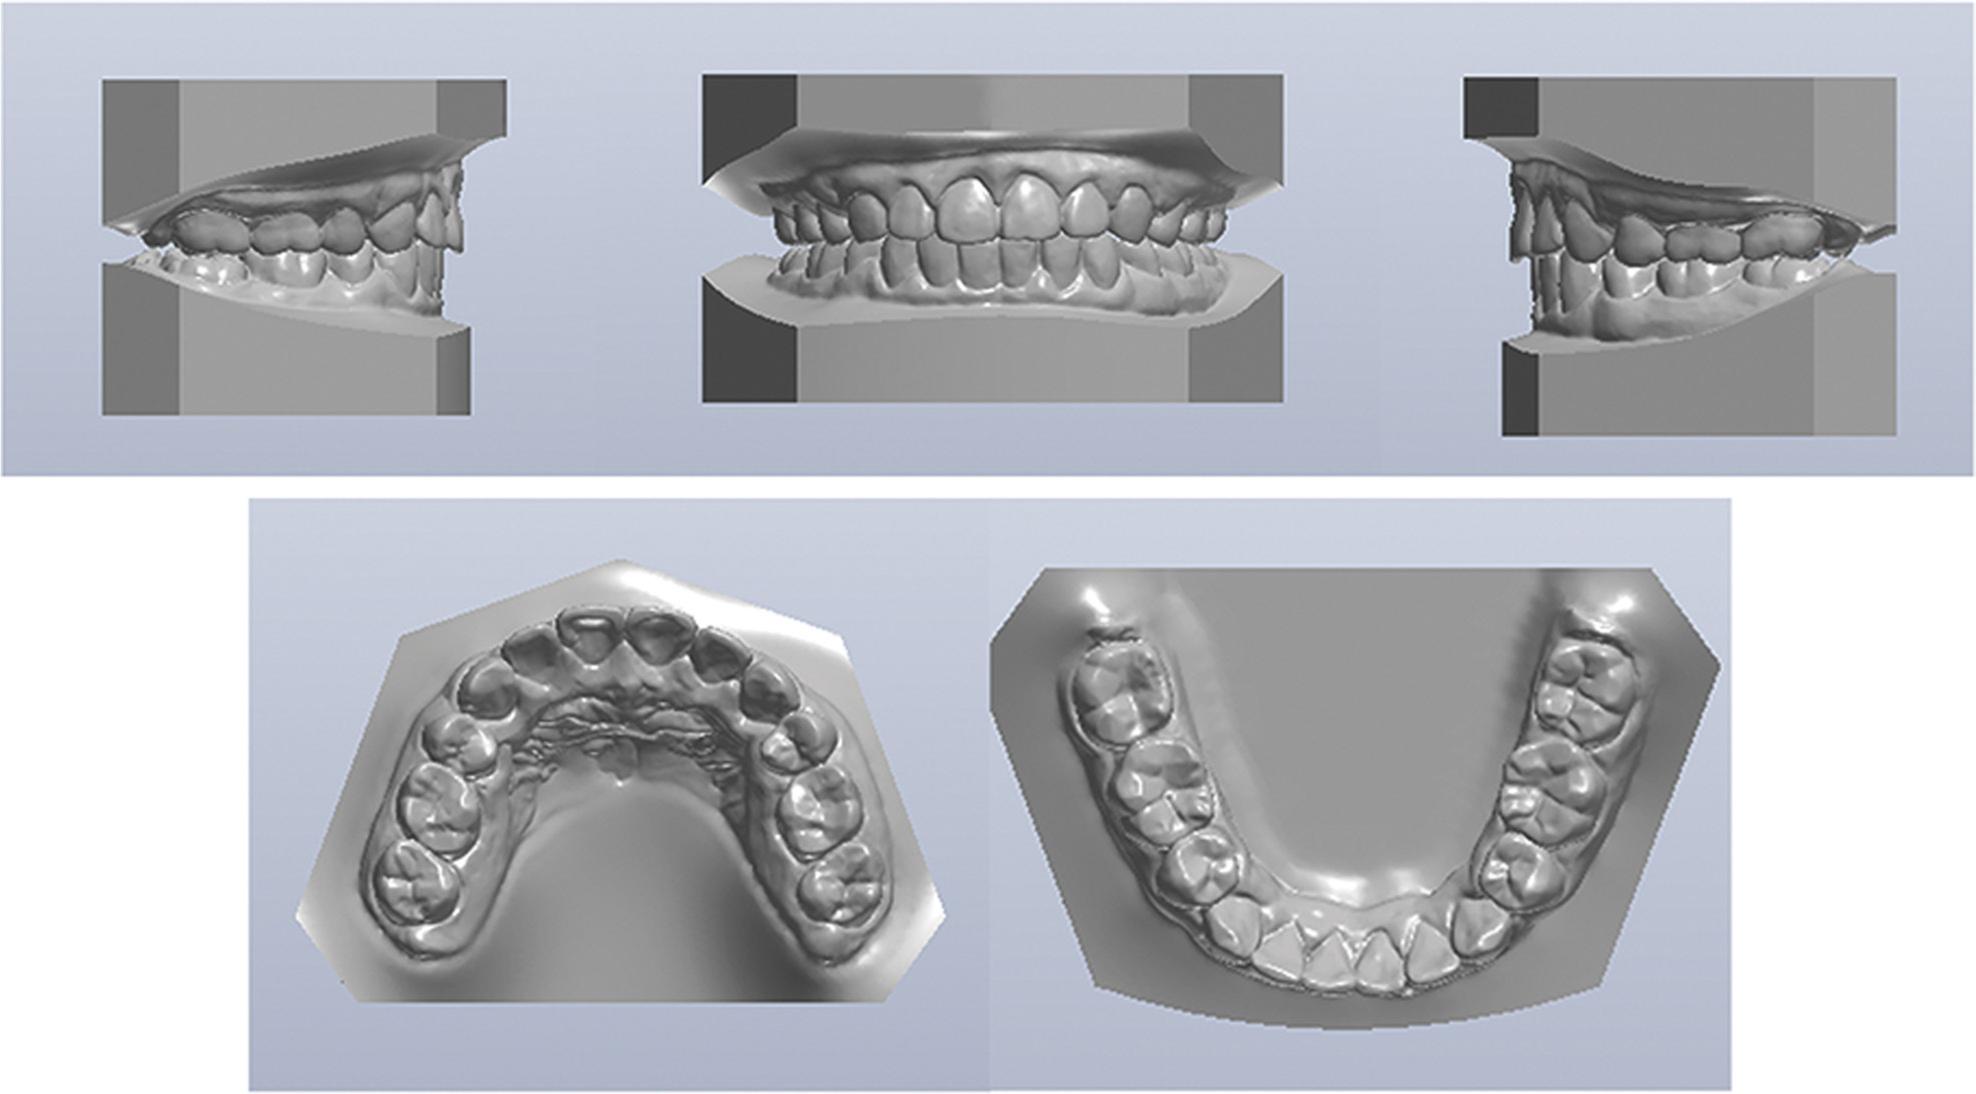

Figure 2.

Pretreatment dental models.

An intraoral examination revealed that the anterior teeth protruded and the mandibular anterior teeth were mildly crowded. The molar relationship was Class I on the right side and end-on Class II on the left side. The overjet was 6.0 mm, and overbite was 5.0 mm. The midline of the mandibular teeth deviated 1.0 mm to the left (Figure 2).